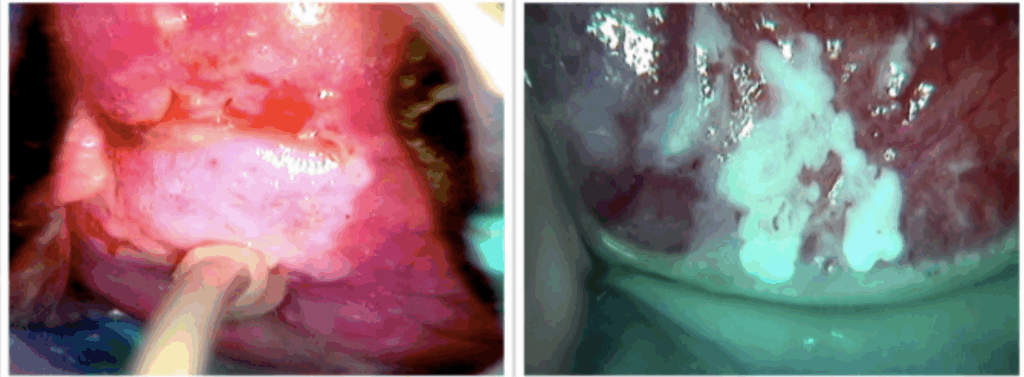

É o exame do colo do útero com um microscópio (colposcópio) após a aplicação de reagentes para realçar áreas suspeitas.

- Objetivos: Selecionar o melhor local para a biópsia e, quando indicado, realizar o tratamento (ver e tratar).

- Aplicação de Ácido Acético (3-5%): Coagula as proteínas. Células com alta atividade de replicação (lesões) ficam com um aspecto branco (epitélio acetobranco).

- Teste de Schiller (Aplicação de Lugol): O iodo cora o glicogênio das células normais de marrom. Células displásicas, pobres em glicogênio, não se coram e ficam amareladas (iodo-negativas ou Schiller-positivo), indicando o local ideal para a biópsia.

- Grau 2 (Maiores): Sugerem lesões de alto grau. Incluem epitélio acetobranco denso, mosaico grosseiro e atipia vascular.

- Junção Escamocolunar (JEC): A visualização completa da JEC é crucial. Se a JEC não é totalmente visível (localizada dentro do canal), a colposcopia é considerada insatisfatória.

A Exérese da Zona de Transformação (EZT), também chamada de Cirurgia de Alta Frequência (CAF) ou LEEP, é o tratamento de escolha para muitas lesões.

- “Ver e Tratar”: Realizar a EZT na primeira consulta colposcópica. Critérios incluem: citologia de alto grau (HSIL, ASC-H), achados colposcópicos maiores, JEC visível, ausência de suspeita de invasão e paciente com mais de 25 anos.

- Conização: É uma excisão em formato de cone, geralmente feita com bisturi de lâmina fria em centro cirúrgico. É preferível para avaliar as margens e é indicada quando a colposcopia é insatisfatória (EZT tipo 3).